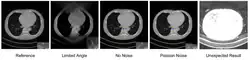

Deep learning methods are widely applied to image reconstruction nowadays and have achieved impressive results in various image reconstruction tasks, including low-dose denoising, sparse-view reconstruction, limited angle tomography and metal artifact reduction. An excellent overview can be found in the special issue [5] of IEEE Transaction on Medical Imaging. One group of deep learning reconstruction algorithms apply post-processing neural networks to achieve image-to-image reconstruction, where input images are reconstructed by conventional reconstruction methods. Artifact reduction using the U-Net in limited angle tomography is such an example application.[6] However, incorrect structures may occur in an image reconstructed by such a completely data-driven method,[7] as displayed in the figure. Therefore, integration of known operators into the architecture design of neural networks appears beneficial, as described in the concept of precision learning.[8] For example, direct image reconstruction from projection data can be learnt from the framework of filtered back-projection.[9] Another example is to build neural networks by unrolling iterative reconstruction algorithms.[10] Except for precision learning, using conventional reconstruction methods with deep learning reconstruction prior [11] is also an alternative approach to improve the image quality of deep learning reconstruction.